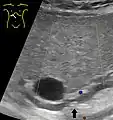

Abdominal ultrasonography of a common bile duct stone

Choledocholithiasis (stones in common bile duct) is one of the complications of cholelithiasis (gallstones), so the initial step is to confirm the diagnosis of cholelithiasis. Patients with cholelithiasis typically present with pain in the right-upper quadrant of the abdomen with the associated symptoms of nausea and vomiting, especially after a fatty meal. The physician can confirm the diagnosis of cholelithiasis with an abdominal ultrasound that shows the ultrasonic shadows of the stones in the gallbladder.